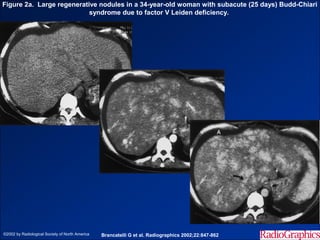

Hình ảnh trên CLVT

- Teo gan ở ngoại vi.

- Phì đại thùy gan trung tâm - phân thùy đuôi.

- Tuần hoàn bàng hệ qua hệ cửa.

- Huyết khối TM cửa – TM dẫn lưu.

- Các shunt mạch máu trong gan.

Figure 2a. Large regenerative nodules in a 34-year-old woman with subacute (25 days) Budd-Chiari

syndrome due to factor V Leiden deficiency.

©2002 by Radiological Society of North America   Brancatelli G et al. Radiographics 2002;22:847-862

• #42 Figure 2a.  Large regenerative nodules in a 34-year-old woman with subacute (25 days) Budd-Chiari syndrome due to factor V Leiden deficiency. (a) Nonenhanced CT scan shows an enlarged liver, and lesions are difficult to identify. (b) Arterial phase CT scan shows multiple hyperattenuating lesions (arrows) with homogeneous marked enhancement. (c) Portal venous phase CT scan shows that the lesions (white arrows) are still hyperattenuating relative to the surrounding parenchyma; the liver demonstrates heterogeneous, patchy enhancement. Note the ascites (A) and the compressed inferior vena cava (black arrow).